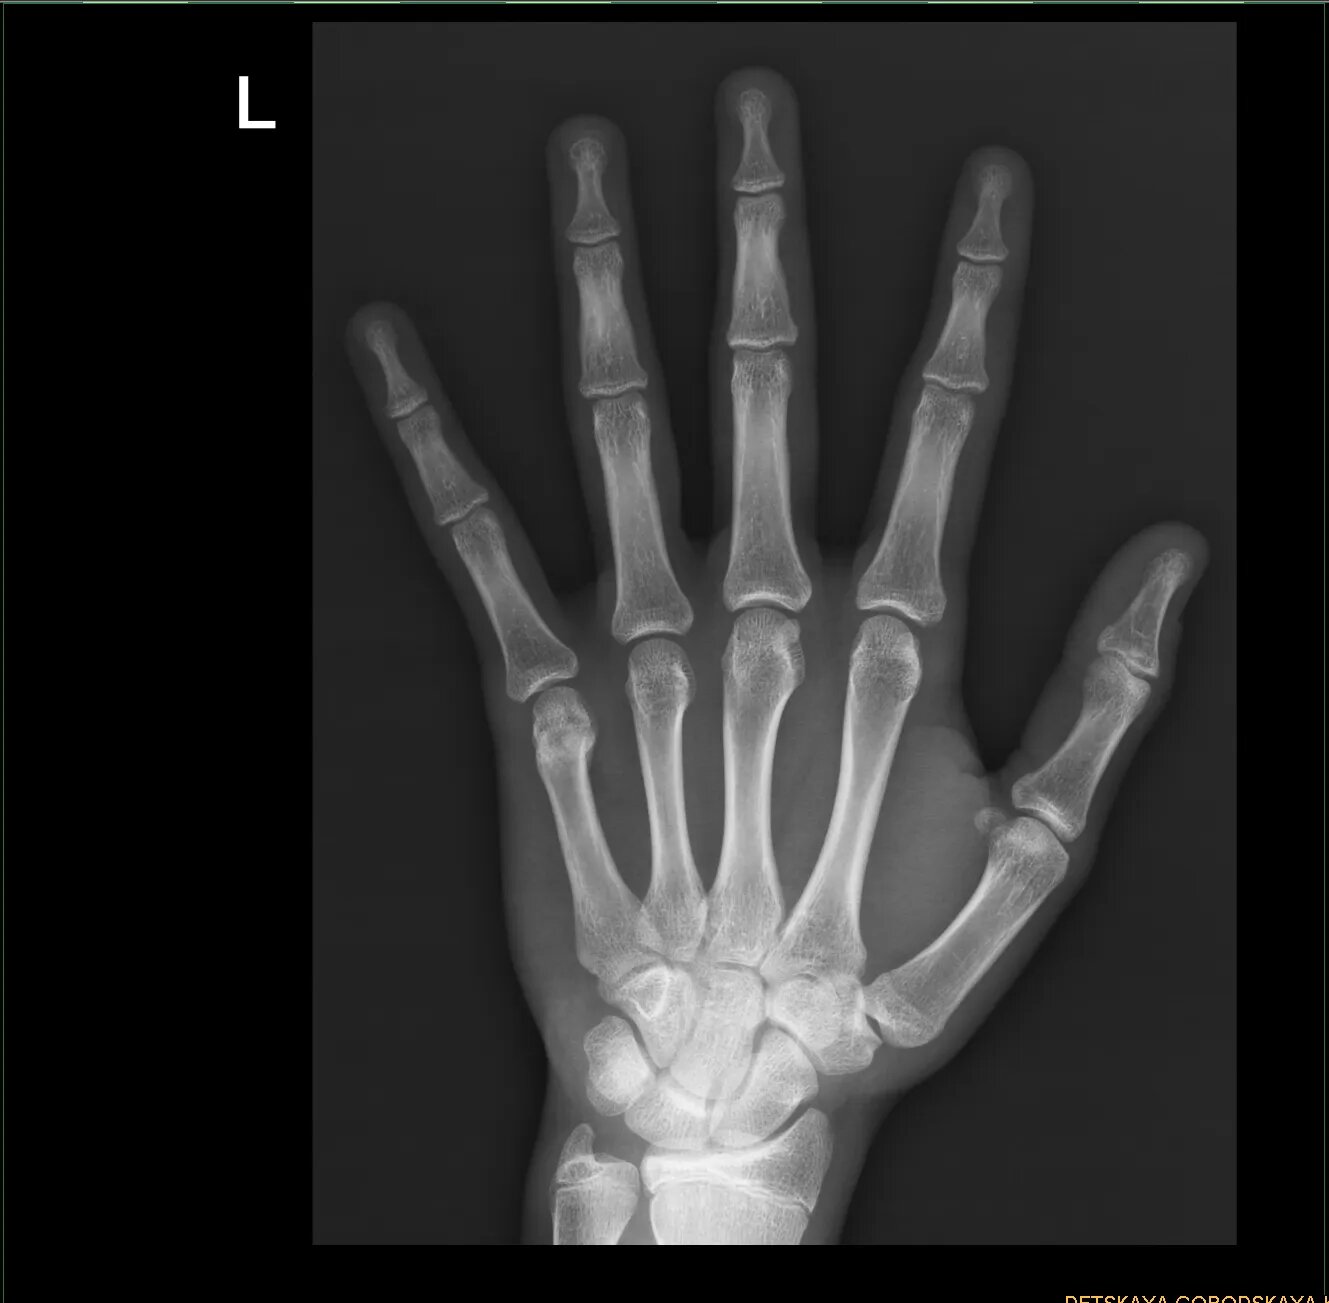

Помогите найти зоны роста костей

Здравствуйте. Зона роста — пластинка гиалинового хряща между эпифизом и метафизом трубчатых костей. На данном снимке обратите внимание на данные структуры в области дистальных концов лучевой и локтевой кости.